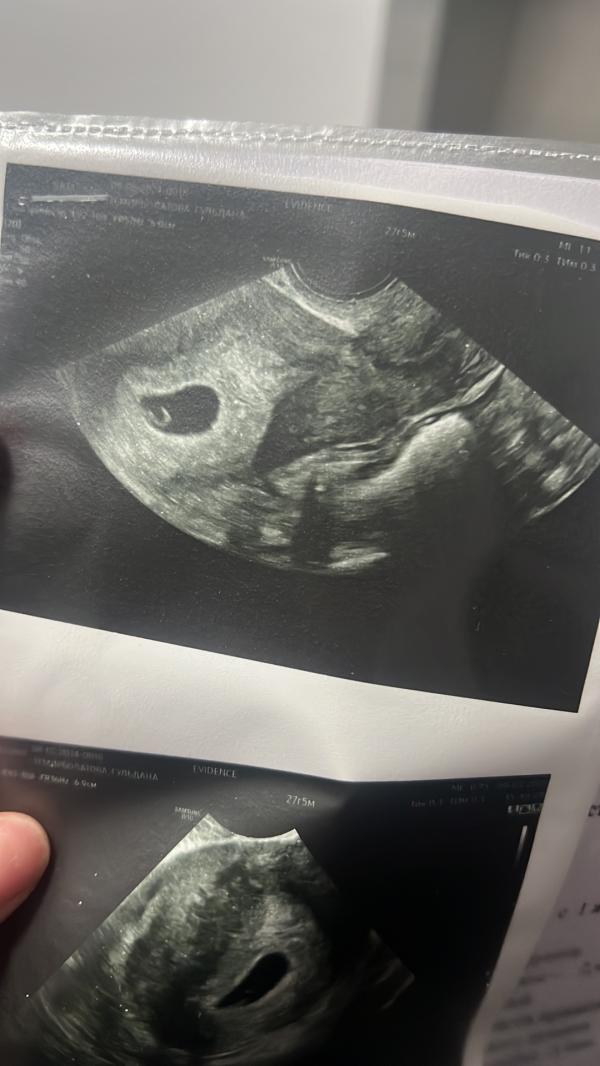

Сходила сегодня на узи

Срок совпал по месячным,

6 недель 1 день🥹

Тьфу тьфу все хорошо,сердечко бьется 🙏🏻

Ходила в клинику Эвиденс